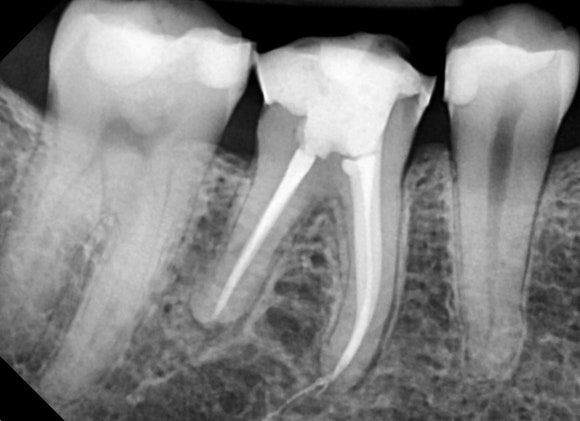

신경치료 완료 후

머리 부분을 일차로 충전해놓은 상태입니다.

이 다음에

치아 머리를 더 정교하게 다듬어서

크라운을 씌워줍니다.

치아와 충전재 사이의 틈이 발생하지 않는 것이

장기적인 성공을 위해 중요합니다.

어금니 신경치료의 마무리는 크라운치료입니다.

신경치료 후 머리부분을 레진으로 충전한 후,

다시 한 번 뚜껑을 씌움으로써

치아에 이중잠금장치를 한다고 보시면 되겠습니다.

어금니의 강한 씹는 힘, 박테리아의 침투로부터

어금니를 보호해주는 기능을 합니다.